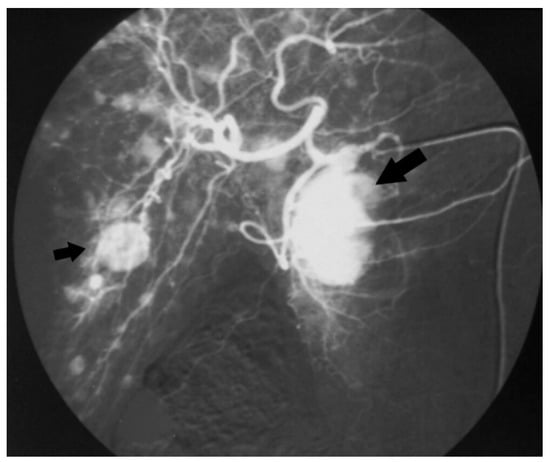

Among 239 patients with a histologically confirmed pNET observed in our unit during the study period, seven (2.9%) patients had a 5-HT-secreting pNET. The study population consisted of four men and three women, with a median age of 64 (range 38–69) years. Only two patients had symptoms related to a carcinoid syndrome with flushing and diarrhoea (Figure 1); all the others presented with a non-functioning pNET. The leading presenting symptom was weight loss in three (43%) patients, and two (29%) patients complained about abdominal pain (Figure 2). One patient had a cervical lymphadenopathy, and another presented with jaundice and ascites due to portal vein thrombosis (Figure 3).

Figure 1. Angiography of the celiac trunk showing a mass in the pancreatic head (big arrow) and multiple liver metastases (small arrow) in a patient with carcinoid syndrome (case n.1).